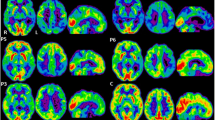

CSF Aβ, total tau, and phosphorylated tau were measured in the PSEN1 M84V carrier, who was cognitively normal at the time of lumbar puncture. CSF Aβ (361.5 pg/ml), total tau (84.93 pg/ml), and p-tau181 (22.02 pg/ml) at 11 years prior to the parental age at symptomatic onset was consistent with other presymptomatic pathogenic mutation carriers but not completely distinct from noncarriers [3, 6]. The PSEN1 M84V carrier produced a mean cortical PiB SUVR value of 1.132 at 15 years prior to the parental age at symptomatic onset and 1.209 at 11 years prior to parent age of disease onset (Fig. 2). A related noncarrier was imaged at 16 years prior to the parent age of disease onset and produced mean cortical PiB SUVR values of 1.086 and 1.039 at 13 years prior to age at disease onset in the parent (Fig. 2). Thus, fluid and imaging biomarkers were consistent with those observed in presymptomatic ADAD mutation carriers.

Pittsburgh compound B (PiB) uptake in the brain of a presymptomatic PSEN1 M84V carrier is consistent with presymptomatic autosomal dominant Alzheimer’s disease mutation carriers. 11C-PiB positron emission tomographic scans were performed longitudinally in a PSEN1 M84V noncarrier and carrier. The color scale for standardized uptake values (SUV) indicate red (high), yellow (medium), and blue (low) PiB retention. EYO Estimated years of onset